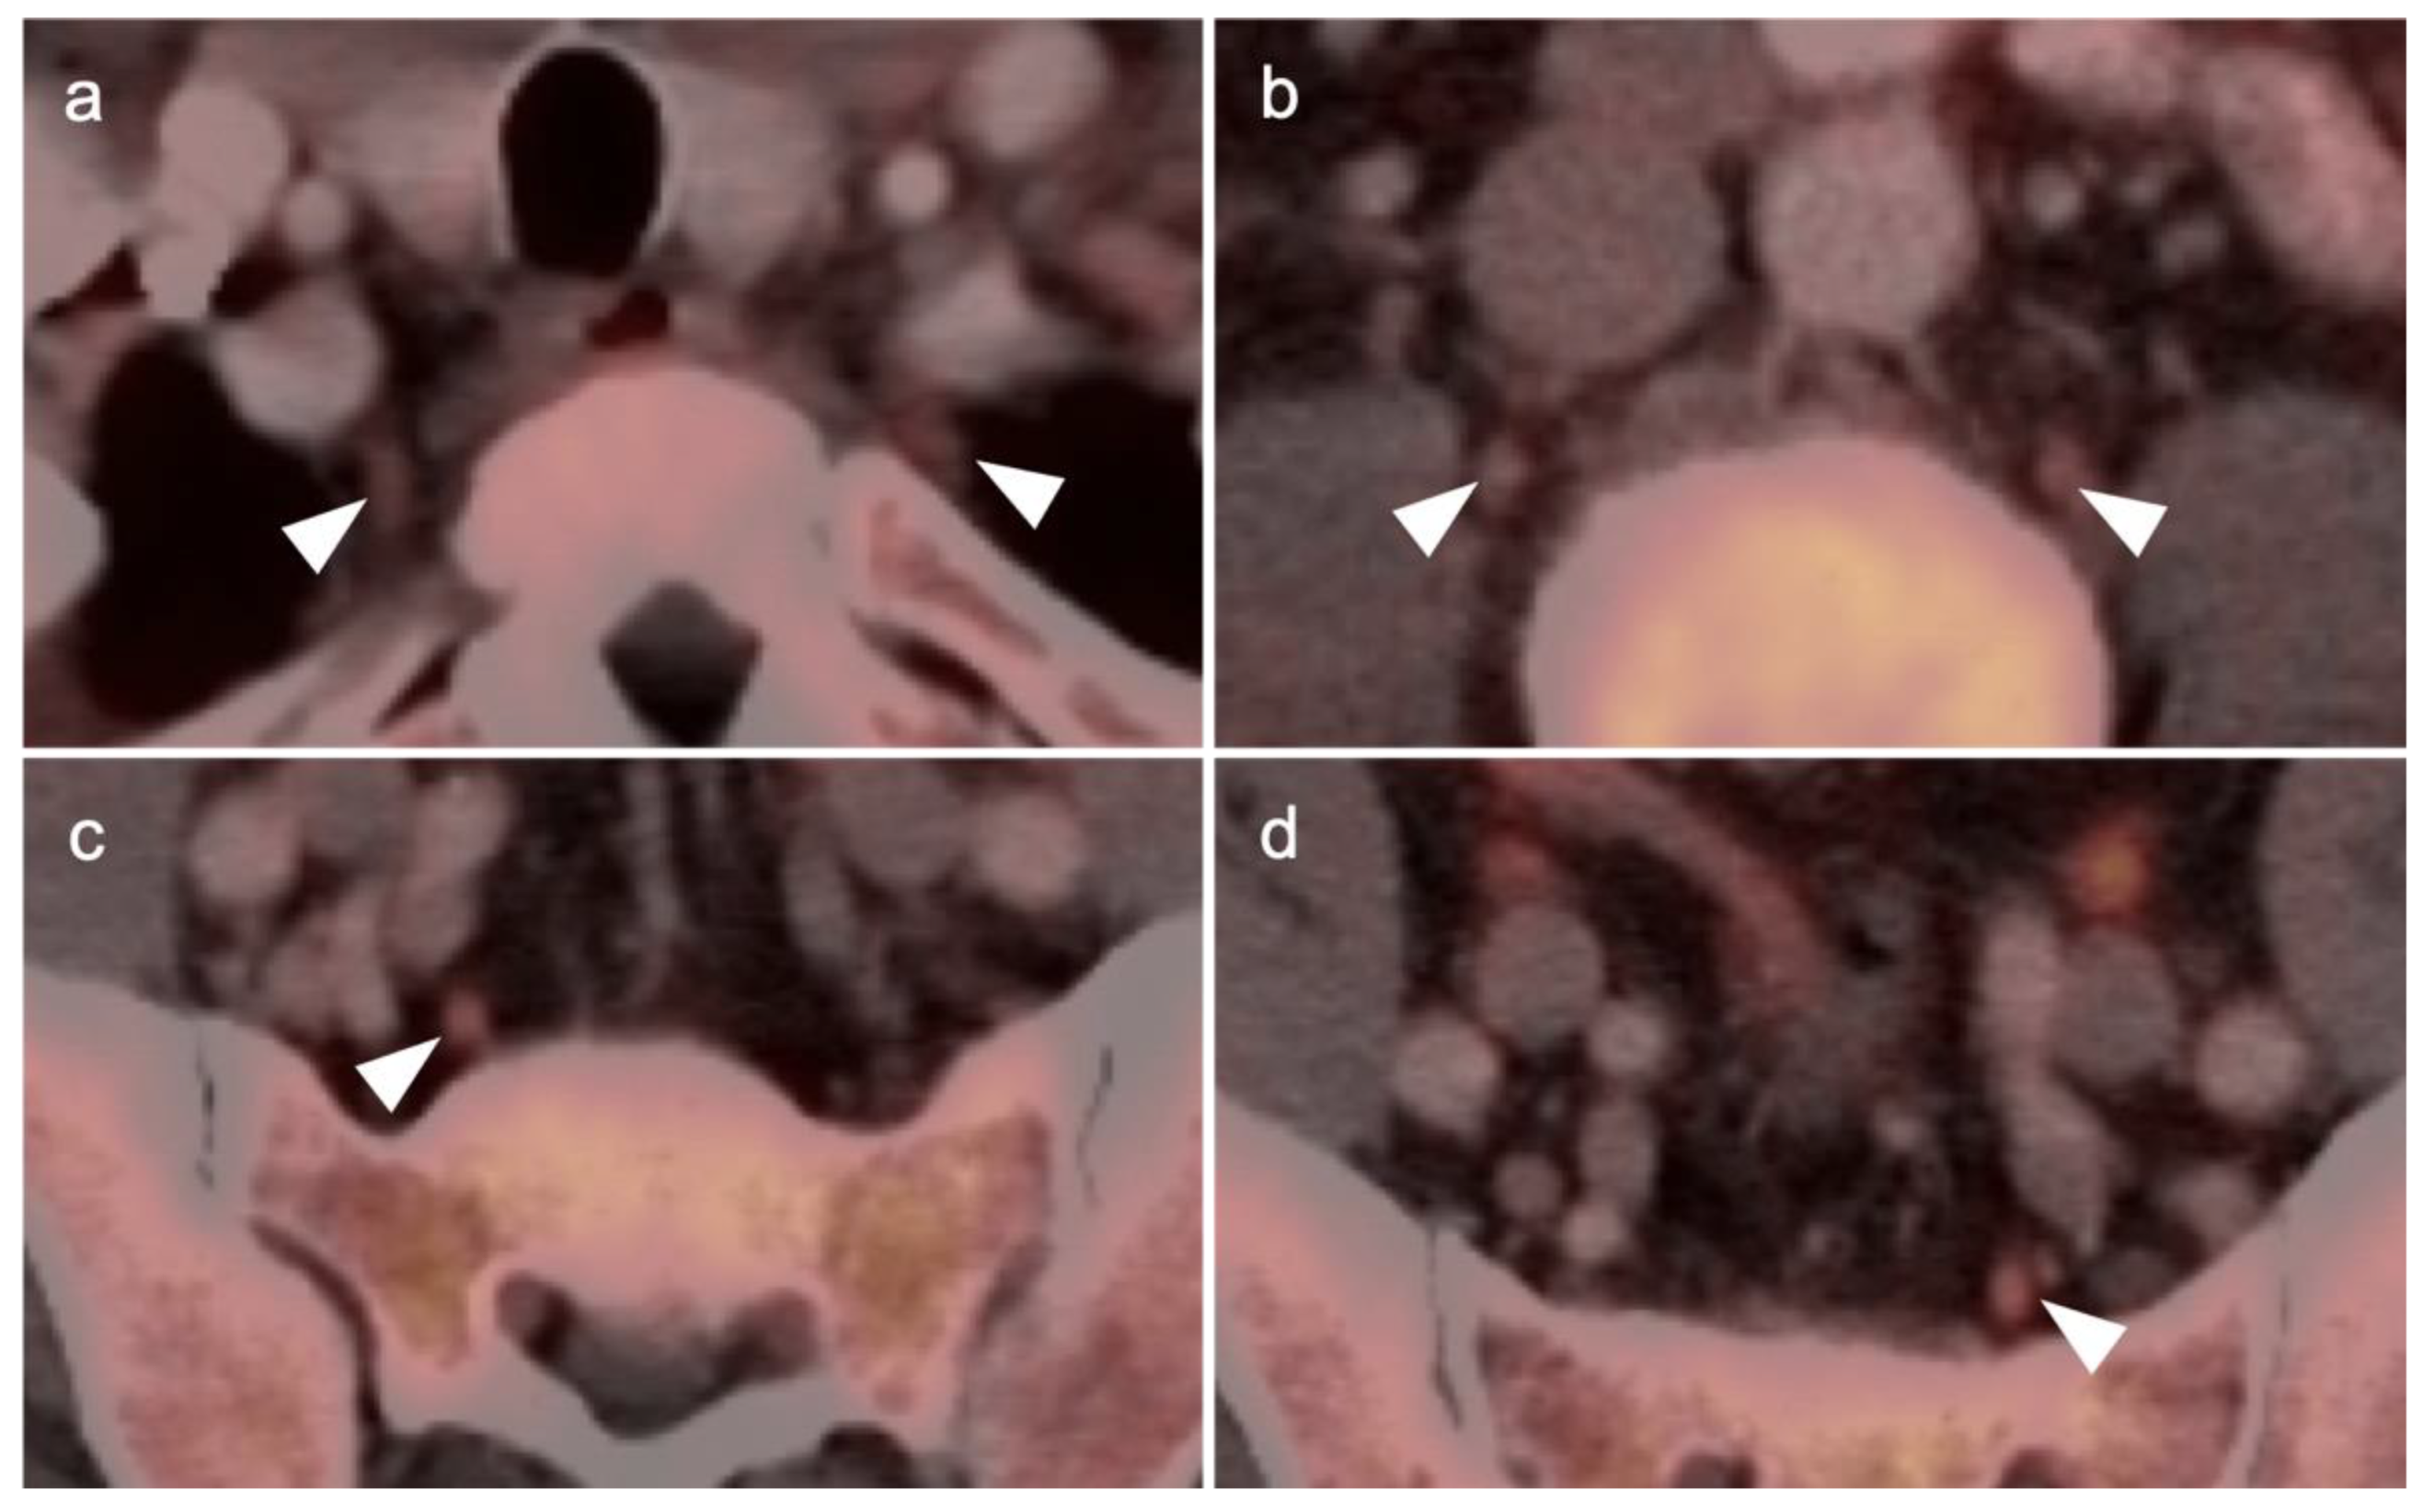

3.1. Prostate Cancer

3.2. Urothelial Carcinoma